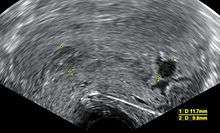

Ultrasound criteria

A review article in The New England Journal of Medicine based on a consensus meeting of the Society of Radiologists in Ultrasound in America (SRU) has suggested that miscarriage should be diagnosed only if any of the following criteria are met upon ultrasonography visualization:[60]

- Crown-rump length of at least 7 mm and no heartbeat.

- Mean gestational sac diameter of at least 25 mm and no embryo.

- Absence of embryo with heartbeat at least 2 weeks after an ultrasound scan that showed a gestational sac without a yolk sac.

- Absence of embryo with heartbeat at least 11 days after an ultrasound scan that showed a gestational sac with a yolk sac.

In addition, signs upon ultrasonography that are suggested to be suspicious for miscarriage, but not diagnostic of it, include:[60]

- Crown–rump length of less than 7 mm and no heartbeat.

- Mean gestational sac diameter of 16–24 mm and no embryo.

- Absence of embryo with heartbeat 7–13 days after an ultrasound scan that showed a gestational sac without a yolk sac.

- Absence of embryo with heartbeat 7–10 days after a scan that showed a gestational sac with a yolk sac.

- Absence of embryo at least 6 weeks after last menstrual period.

- Amniotic sac seen adjacent to yolk sac, and with no visible embryo.

- Yolk sac of more than 7 mm.

- Small gestational sac compared to embryo size (less than 5 mm difference between mean sac diameter and crown–rump length).